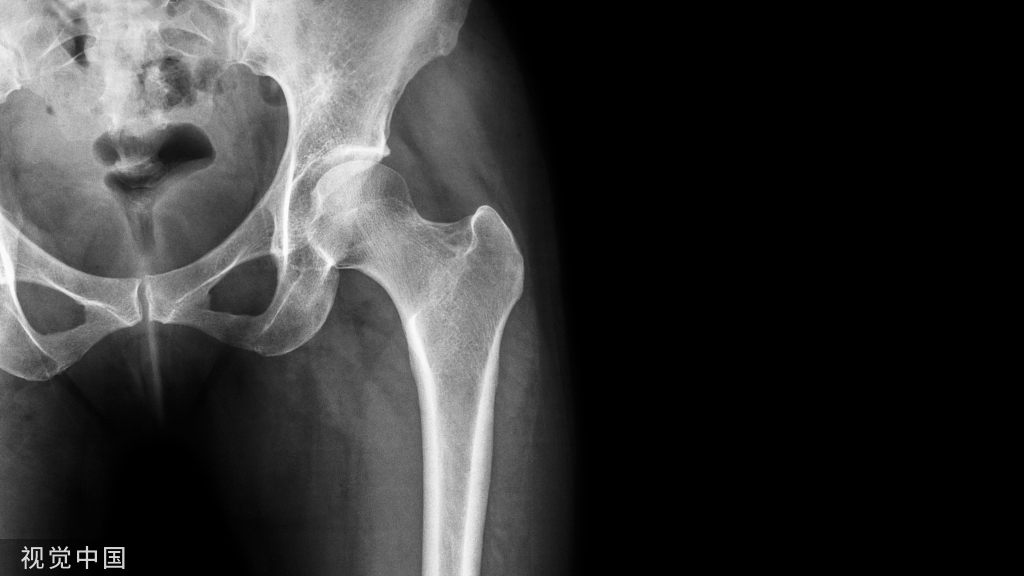

3、核磁共振检查时,非金属的氧化锆对X线无任何阻挡,核磁共振检查时都不需要拆掉假牙,省去很多麻烦。